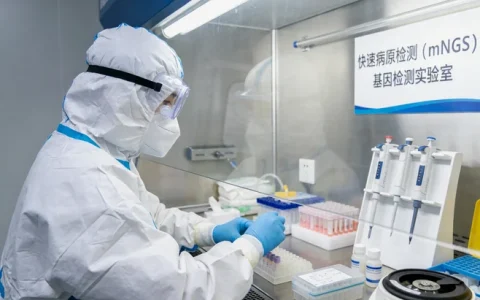

流程上,其实比大家想象的要简单。核心步骤就三步:说到这个,需要由临床医生(通常是消化内科、内分泌科或肿瘤科的医生)根据病情判断是否有必要进行检测,并开具申请。还有一点,采集样本,最常见的是用之前手术或穿刺取得的那一小块肿瘤组织(石蜡包埋块或切片),如果组织无法获取,用血液样本也可以进行部分分析。最后提一嘴,样本会被送到有资质的基因检测实验室进行分析。

大家最关心的“靠谱”问题,关键在于两点:技术平台和解读能力。现在主流的检测技术,比如二代测序(NGS),一次性能分析几十甚至上百个相关基因,效率高,精度也够。但更关键的是后续的生物信息分析和临床解读——海量的基因数据里,哪个突变有意义?这个意义对临江的这位具体患者意味着什么?这需要实验室有强大的数据库、专业的生物信息团队和懂临床的解读专家。在临江本地,像 万核基因 这样的专业检测机构,其价值就在于提供了从样本接收、标准化检测到出具具有临床指导意义报告的一站式服务,并且能与临江各大医院的临床路径衔接,让您不用奔波外地,就能获得符合国际国内指南的检测服务。